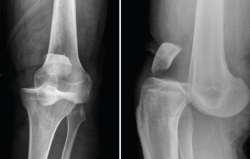

1.1.2. Tibia (Figura 2)

Figura 2. Radiografías anteroposterior y lateral de rodilla: fractura con varios trazos de meseta tibial externa.